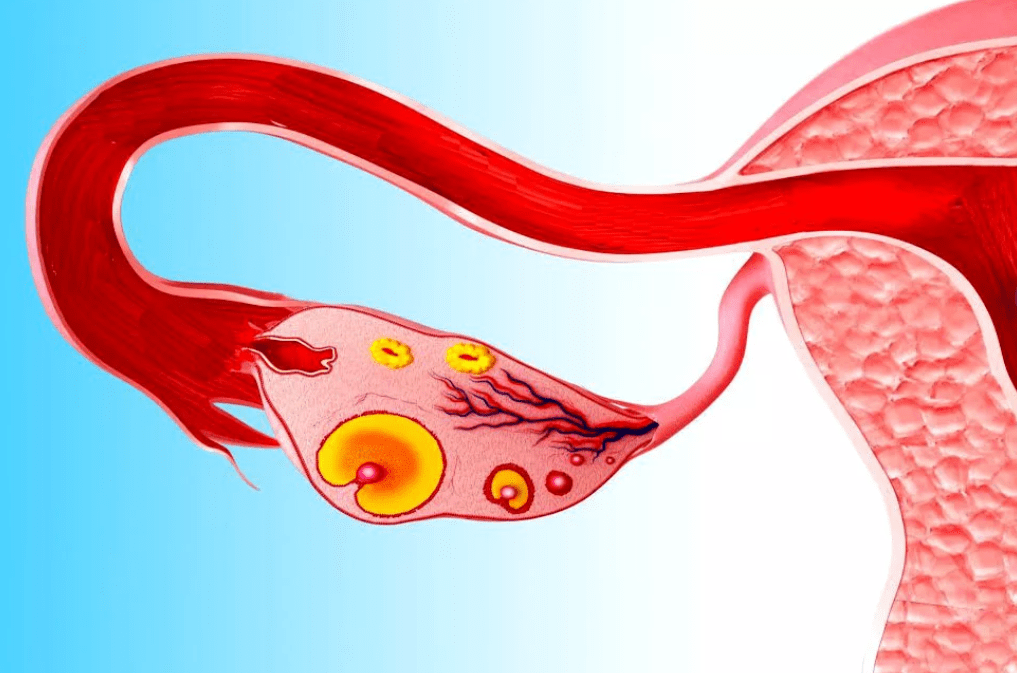

Воспаление яичника, или оофорит — одна из причин женского бесплодия. Сегодня поговорим о симптомах этого заболевания и о том, как происходит лечение.

Причины воспаления яичников

К главным причинам оофорита у женщин относятся: